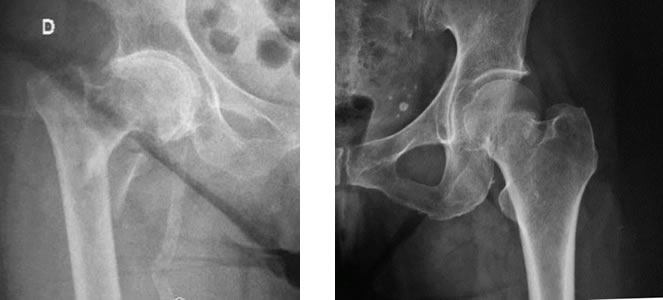

La articulación de la cadera comprende la región superior del fémur y el acetábulo. Se considera fractura de cadera a aquellas que involucran la parte superior del fémur. Las fracturas de cadera son lesiones graves, con repercusión en el estado general del paciente y requieren un tratamiento específico dependiendo del tipo de lesión. Se asocian a una elevada morbimortalidad, con un 30% de mortalidad en el primer año en paciente añosos.

La factura puede ubicarse en el cuello del fémur o en la región intertrocantérica. La característica de la fractura, la ubicación, la edad y la expectativa de vida y funcional del paciente determinaran el tipo de tratamiento a seguir.